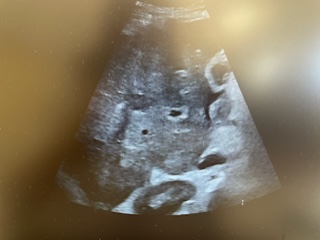

Descripción de los hallazgos ecográficos y las imágenes más relevantes para la resolución del caso

Realizamos POCUS en consulta y objetivamos líquido libre abdominal, así como hígado heterogéneo con distorsión grosera del parénquima, donde se objetivan dos lesiones hipoecogénicas de menos de 2 cm de longitud.